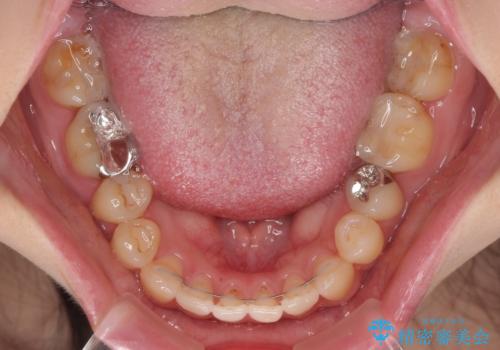

- 矯正装置

- 審美装置

- 治療期間

- 10ヶ月

治療開始から8ヶ月ほどで遠方への転勤が決まりましたが、歯列は概ね整っていたため、その後は東京出張を狙って治療を終える処置を行うことができました。